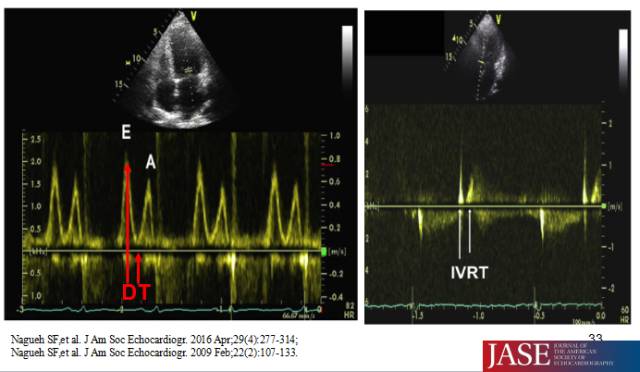

◆二尖瓣口舒张期血流频谱E峰、A峰、E/A比值及Valsava动作E/A 比值变化(Val. ΔE/A)

◆二尖瓣口E峰减速时间—DT、等容舒张时间—IVRT

◆舒张早(晚)期二尖瓣环运动速度e’(a’)、E/e’比值

多普勒超声指标正常值范围

HFpEF—左室舒张功能指标参考值范围

二尖瓣口舒张期血流频谱指标1

二尖瓣口舒张期血流频谱指标2